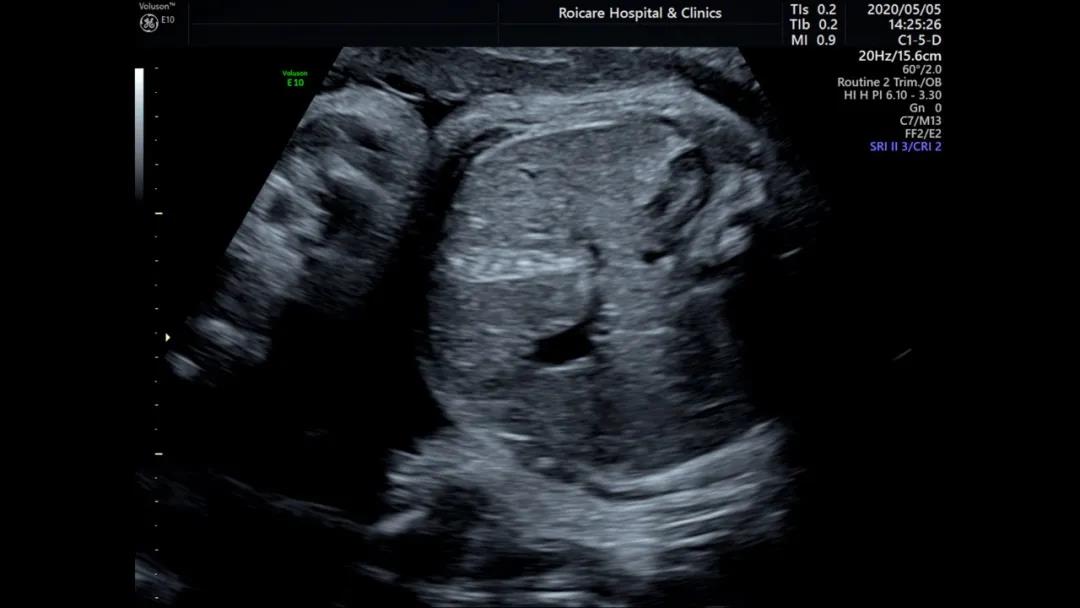

1.心脏强回声

心室强光点是孕期最为常见的强回声,这些孤立的强回声不会影响心功能,也不是胎儿心脏的结构异常的表现,一般孕晚期会消失,有时会追溯到新生儿期。其在正常胎儿中发生率在2%-5%。

宝妈们遇到这样的报告,如果染色体异常筛查低风险,我们可以选择乐观一些。但对本身存在染色体异常高风险的人群还是要更谨慎一些,要听听产科医生的意见。